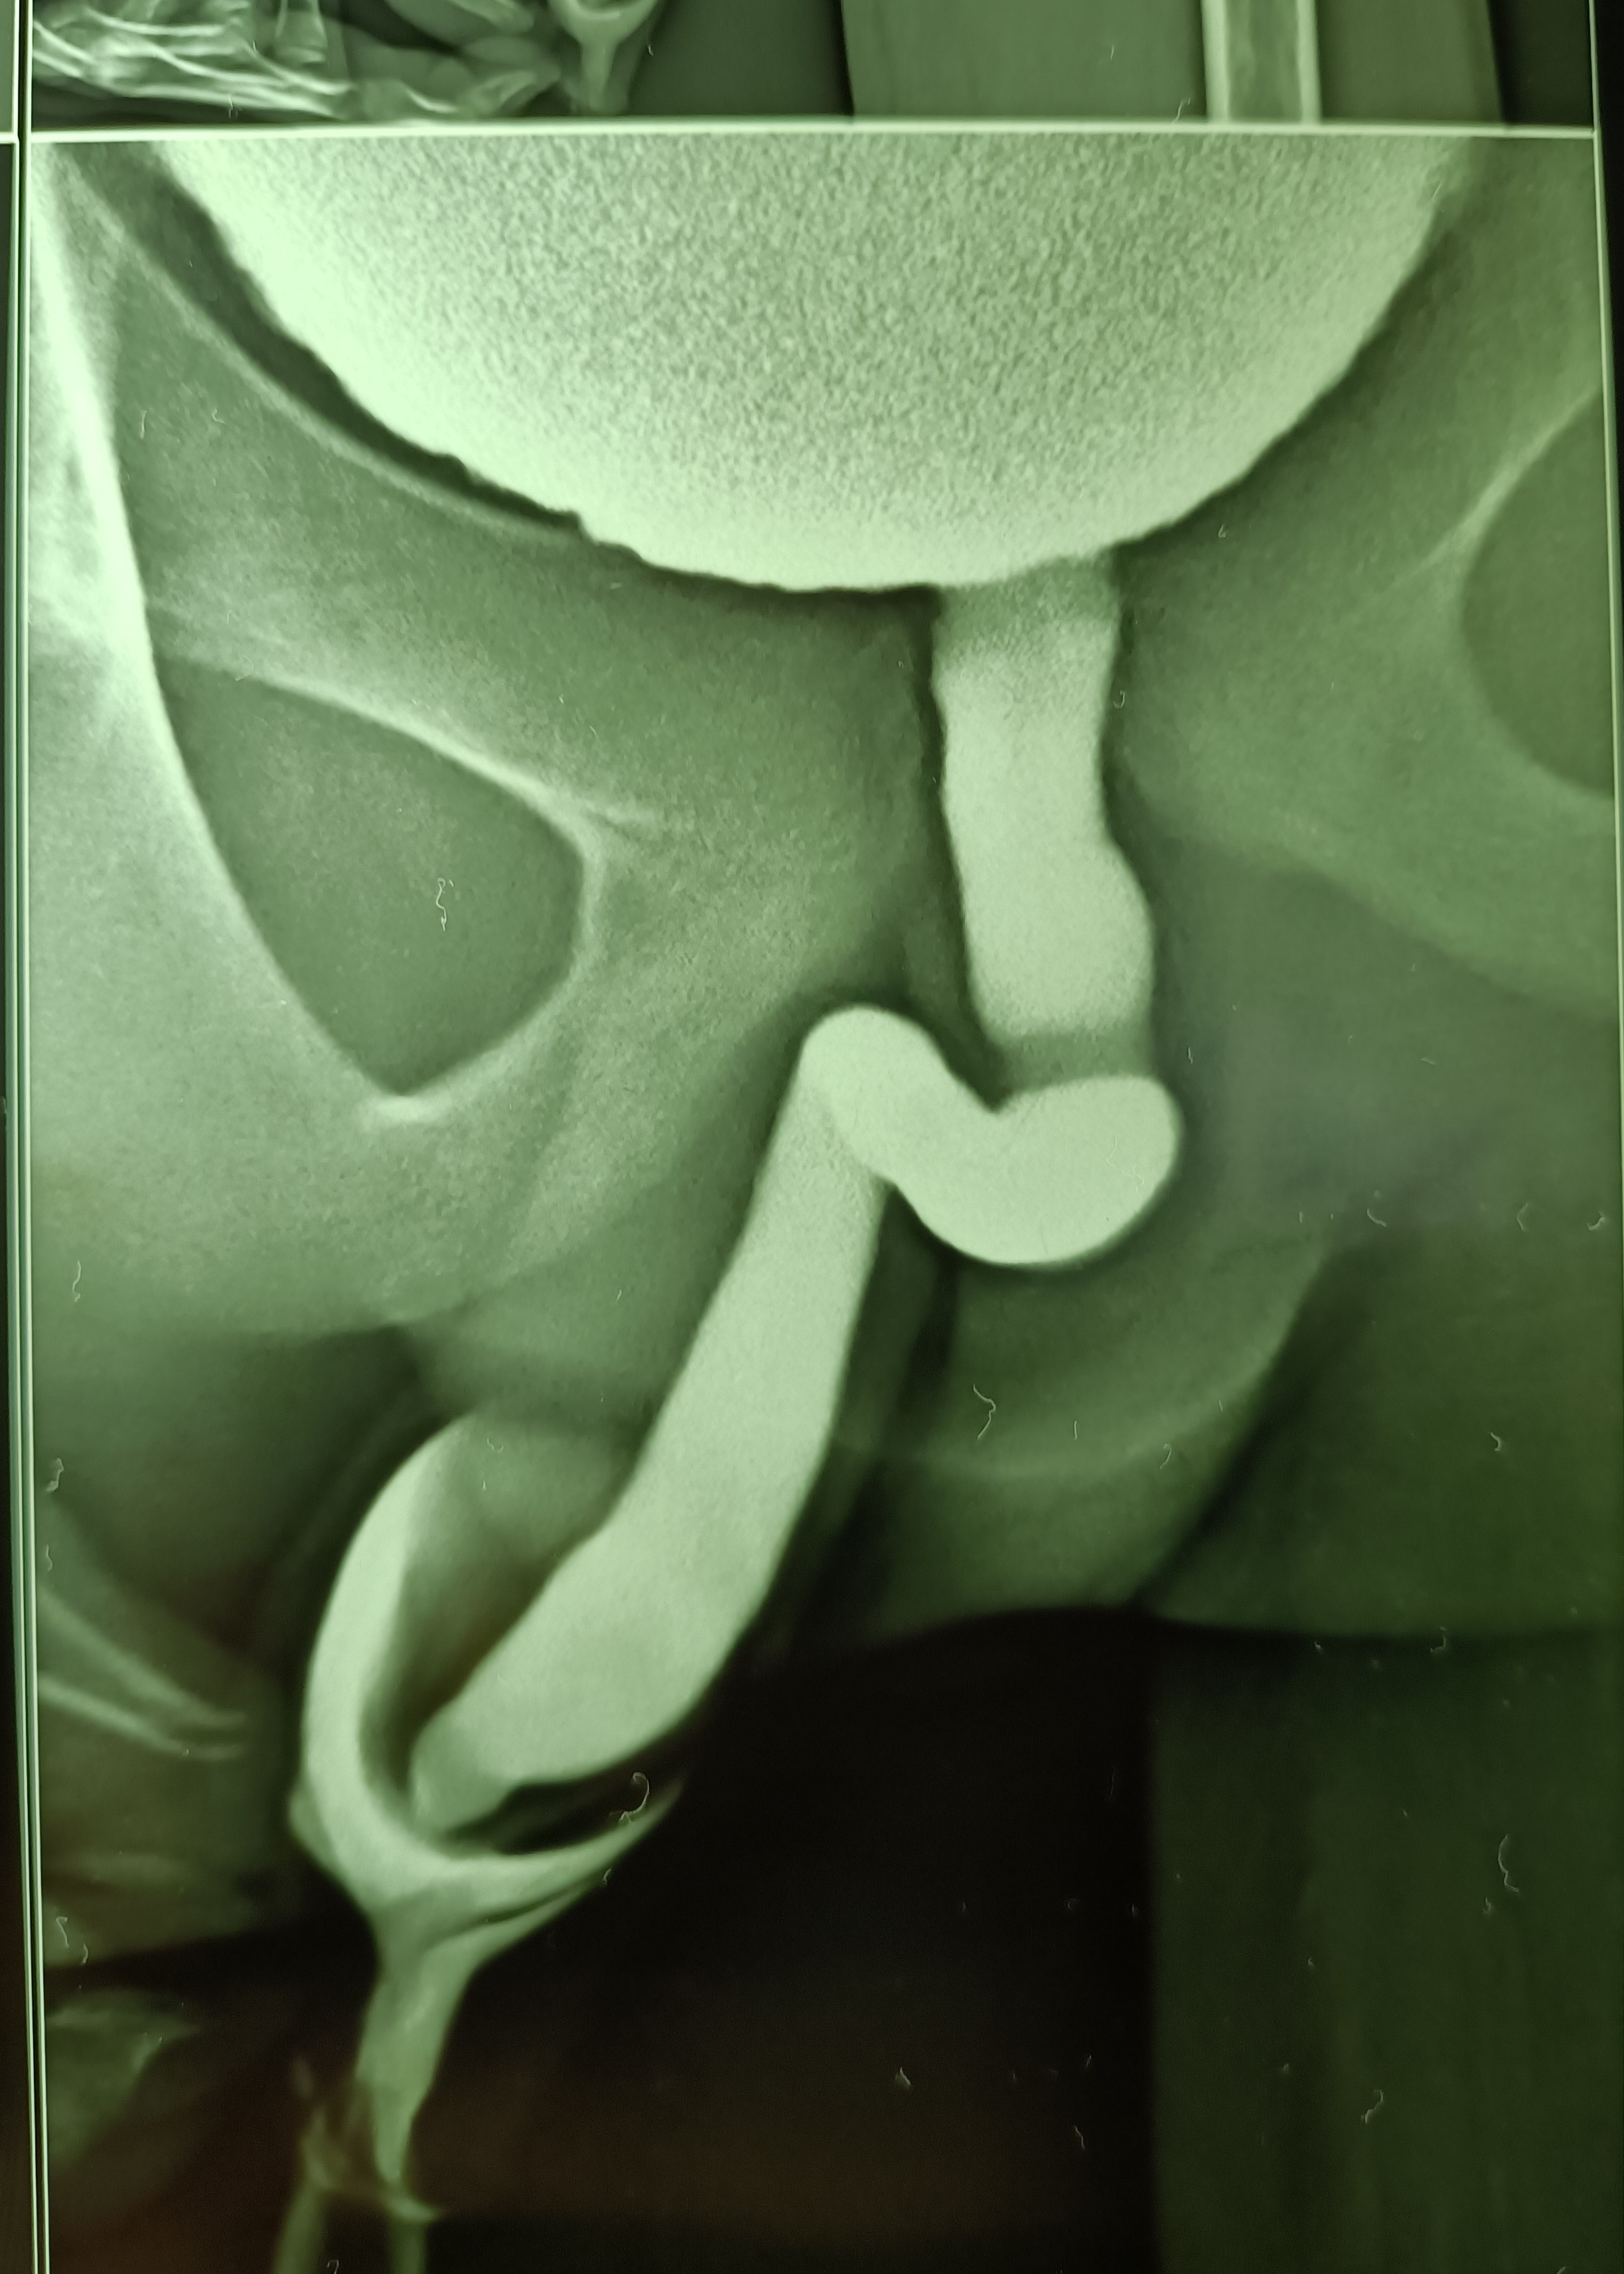

A 13 years old boy presented with acute painful retention of urine at night (it was actually an acute-on-chronic retention, as it came to light later) and since catheterization could not be done due to the tightly stenosed preputial opening, the bladder was emptied with a suprapubic needle. An ultrasound scan in the morning reported circumferential wall thickening of the urinary bladder and a V-shaped deformity of the bladder neck, suggesting a diagnosis of posterior urethral valves.

Paediatric surgical consultation was obtained and an MCU was suggested. This was done and suggested a diagnosis of neurogenic bladder while ruling out posterior urethral valves.

A routine circumcision was performed the same day and the child remains well thereafter.